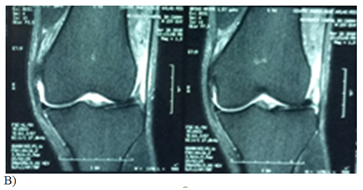

Figure 1 Case: Patient 28 years old male, 10 day history of sports injury with complete patella tear accident: we proceeded to a repair using trans-osseous patella suturing with vicryl 2 and reinforcement semitendinosus.

B, C etc- coronal and axial section in particular sequence of proton density